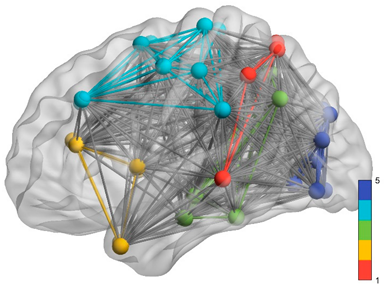

2.5. Regions of Interest

3. Results